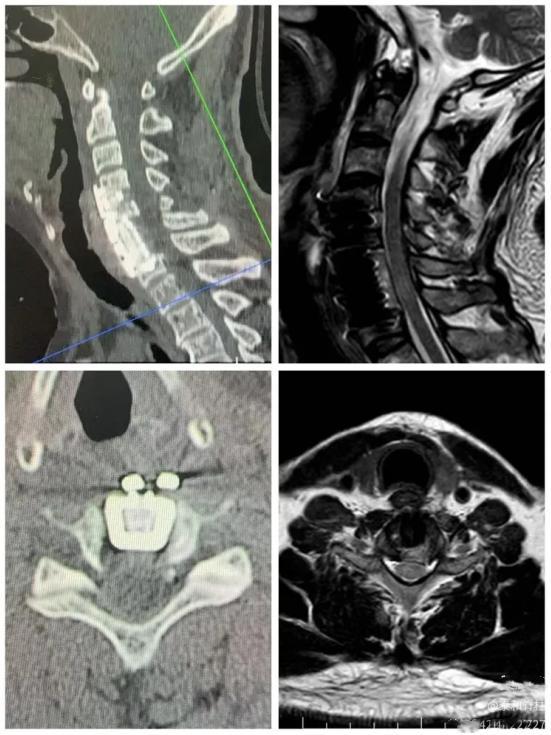

经过积极治疗和康复后,罗先生恢复速度远超预期。曾经走路不稳、随时可能瘫痪的他,慢慢能够下床、站立、独立行走,身体一天天向好!术后复查影像资料显示:脊髓恢复了正常形态,椎管减压非常成功!后续进一步进行康复治疗,重返工作岗位、重回事业巅峰,指日可待!